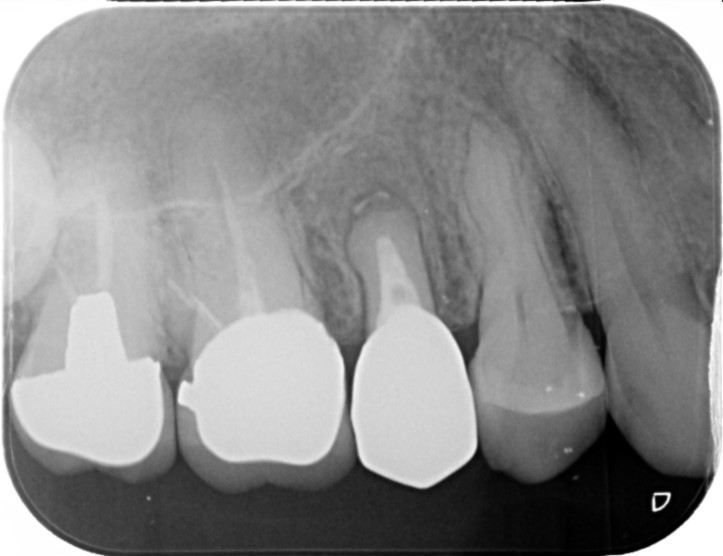

画像

R5.10

R7.11

治療部位 右上5、6番

費用 約140000円

治療期間 9ヶ月

ともに違和感を感じ、被せ物を外して根っこの治療へ。

再度土台も建て直し、被せ物を作りかえました。

治療の途中、この歯にできる治療はここが最後になることもお話し、

抜歯になる可能性もきちんと患者様と共有しながら治療を進めていきました。